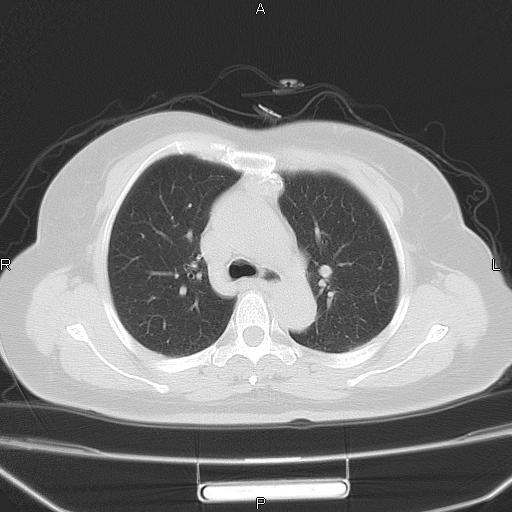

胸腺瘤

女、63Y 双眼睑下垂,早轻晚重。 胸腺瘤???

结果胸腺瘤